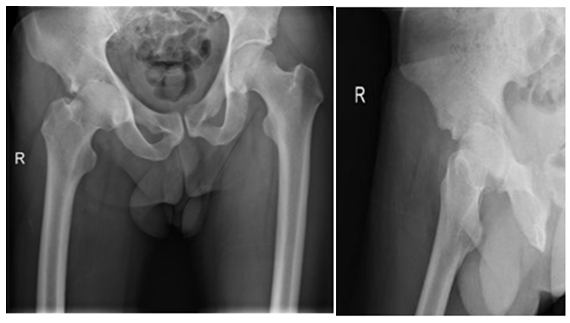

Two stage treatments consisted in an initial surgery through a posterior approach, debridement of inflammatory tissues, neck osteotomy and acetabular reaming adding a temporal non-articulated antibiotic impregnated cement spacer for the resected femoral head. 6 weeks after surgery when intravenous antibiotic treatment was completed and laboratory inflammatory parameters were controlled, a second stage surgery was planified: Conversion to a hybrid arthroplasty for the first case and a non cemented total hip arthroplasty for the second case (Figure 1) (Figure 2).

Figure 2: 44 year male patient. A and B images show hip articular damage, C, D, E, F MRI shows a purulent collection and articular effusion. G image of the spacer H and I postoperative x-ray showing the non cemented total hip arthroplasty. Differed anatomy showed chronic inflammation compatible with osteomielitis for both cases, staphylococcus aureus meticilin resistant organism was isolated. Harris Hip Score of 96 at 2 year follow up, infection markers controlled, and no complications were reported.